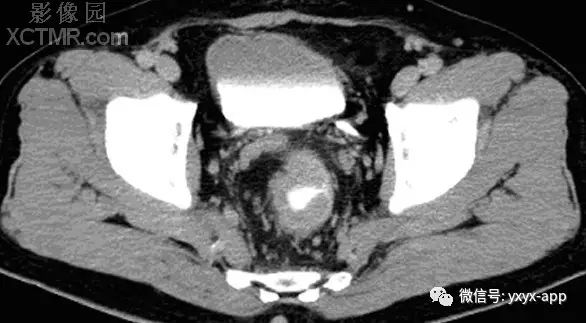

【影像表现】 钡灌肠:直肠与乙状结肠起始部可见不规则充盈缺损(图1箭头),肠管见偏心性狭窄;粘膜皱襞紊乱,纠集(图2、3箭头)。 CT:直肠壁不均匀增厚,见软组织影突入直肠腔内,增强扫描中度强化,周围脂肪间隙欠清楚,直肠后方可见肿大淋巴结(箭头)。肝脏体积增大,肝内密度欠均匀,可见多发弥漫不均匀低密度区,增强扫描病灶显示更加清楚,呈多发结节样低密度影,脾周及胆囊窝周围可见少量液性低密度影。

【诊断】 直肠癌

CT:(1)肠壁增厚,增厚的肠壁黏膜面多明显凹凸不平。(2)腔内肿块影,偏心性,呈分叶状或不规则形,与正常肠壁分界清楚,肿块表面可见小溃疡,呈火山口样。(3)肠腔狭窄,且为非对称性。(4)增强扫描可见较明显异常强化。(5)浆膜及临近器官受侵表现。